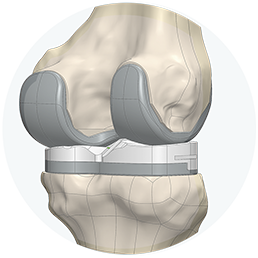

Consigue una sensación más natural

Prótesis de rodilla 3D está diseñada para seguir la forma y el contorno de la rodilla de cada paciente, proporcionando un mayor potencial para su rodilla con una sensación más natural.